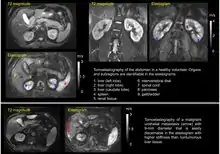

Tomoelastography (from ancient Greek τόμος tomos, “slice” and elastography – imaging of viscoelastic properties) is a medical imaging technique that provides quantitative maps of the mechanical properties of biological soft tissues with high spatial resolution (called elastograms). It is an advancement of elastography[1][2][3] in that it generates unmasked maps of stiffness and viscosity across the entire field of view that can be captured with a given imaging modality. Medical ultrasound and magnetic resonance imaging (MRI) are the most commonly used imaging modalities for elastography. Classical elastography only measures stiffness in a limited region, such as at a depth of 6 cm in the liver or in a selected liver lobe, and thus cannot provide an overview of the adjacent tissues or organs. Tomoelastography, on the other hand, is a radiological imaging method that allows estimation of quantitative mechanical parameters of all organs and structures in the field of view.[4] Moreover, tomoelastography does not rely on a single, specific imaging modality. While it has been introduced and is mostly performed using magnetic resonance elastography (MRE),[2] tomoelastography can be extended to other imaging techniques as well.

Tomoelastography requires external driver systems, which can efficiently generate shear waves throughout the entire field of view including tissues deep within the body. Multiple drivers can be combined such that waves propagate from the surface into the body from different directions to enable full illumination of larger regions with shear waves. Tomoelastography often employs mechanical vibrations at several driving frequencies for multifrequency wave analysis in order to stabilize inverse problem solutions for viscoelasticity reconstructions. A standard way of multifrequency viscoelasticity reconstruction is based on phase gradient analysis of plane waves[5] whereas other methods employ solutions of the Helmholtz equation.[6][7][8] The feasibility of tomoelastography was first demonstrated in the human abdomen using multifrequency MRE, where it was possible for the first time to display stiffness values (quantified as shear wave speed in m/s) across the entire axial MRI slice.[5] Although the elastograms are quantitative maps, tomoelastography images, like other radiological images, are often presented in standard gray-scale which gives more perceptual contrast to the subtle nuances than the color-scale.

Currently, most applications of tomoelastography are based on MRI, which is why tomoelastography is often referred to as an advanced MRE technique. Multifrequency-MRE based tomoelastography has been used for the diagnosis of diffuse liver disease,[9][10][11] renal diseases such as renal allograft dysfunction,[12] lupus nephritis,[13] and immunoglobulin A nephropathy (IgAN).[14] In addition, tomoelastography has been used for cancer imaging. In the liver, viscoelastic parameters of lesions less than 1 cm in diameter could be quantified for diagnostic purposes.[15] Pancreatic cancer has been shown to be abnormally stiff compared to surrounding tissue, resulting in a large tumor contrast in elastograms.[16][17] In the prostate, tomoelastography has been able to distinguish cancer from benign lesions.[18]